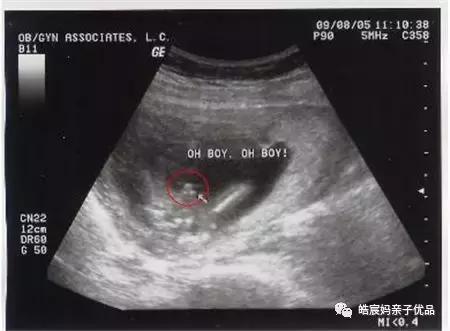

一般在用早孕棒测出怀孕之后,或者是用排卵试纸检测到呈阳性时就可以马上去医院做B超了,B超是诊断出怀孕的最正确可靠的方法。最早是在怀孕5周就能检测出来,就是在月经过期一周,在B型超声波上就会显示出子宫里面有圆形的光环,这也叫做妊娠环,环内的暗区就是羊水,其中还能够看见有节律的胎心搏动。

一般是怀孕在4个月左右的时候就能够通过B超来确定胎儿的性别,但是要看胎位的情况,胎位好就看的比较清晰,但是也不要太相信这个判断。对于判断胎儿的性别来说,最直接的方法就是做B超检查,B超下可以清晰的看清楚胎儿的各个器官和脸部,其中也包括生殖器。